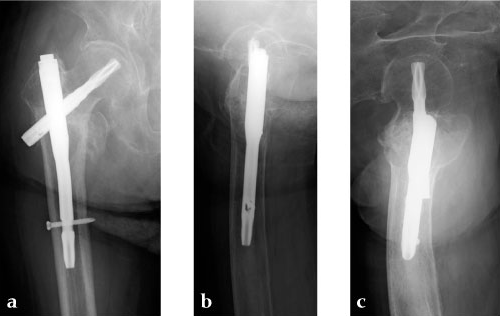

Case 2: Elderly patient with fall injury

Case provided by Takeshi Sawaguchi, Toyama, JP

An 85-year-old Japanese woman fell down at her home. She sustained an AO 31-A2.1 fracture. The images indicate various stages of the operation, using the PFNA Asia.